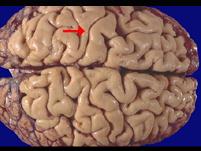

如图箭头所示为大脑哪个部位 ( )A、枕叶B、额叶C、旁中央小叶D、中央后回E、中央前回

问题 如图箭头所示为大脑哪个部位 ( )

选项 A、枕叶 B、额叶 C、旁中央小叶 D、中央后回 E、中央前回

答案 D